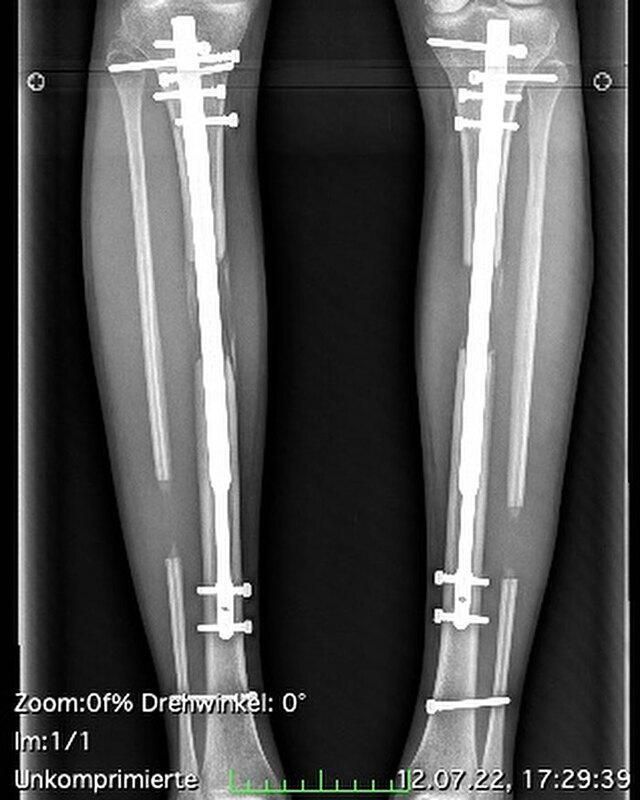

She saw the change as liberating—an investment in herself, her future, her confidence. But the procedure was extreme. It required breaking her thigh and shin bones, inserting metal rods, and slowly stretching her legs over time. The process was long, painful, and medically demanding.

Limb-lengthening surgery is one of the most complex reconstructive procedures in modern medicine. It begins with an osteotomy, where surgeons cut the patient’s bones into two distinct segments. These segments are then connected using either:

- External fixators—metal frames attached outside the body

- Internal rods—magnetic or mechanical devices placed inside the bone

Each day, the patient adjusts or activates the device to create a one-millimeter gap between bone segments, allowing new bone to form.

It is a slow, grueling, and highly invasive process. Clothes don’t fit, walking becomes difficult, and the body is forced to adapt to unnatural stretching. Pain and swelling are expected companions.

Theresia faced these challenges repeatedly through multiple surgeries on her left leg alone. And the consequences soon caught up with her.